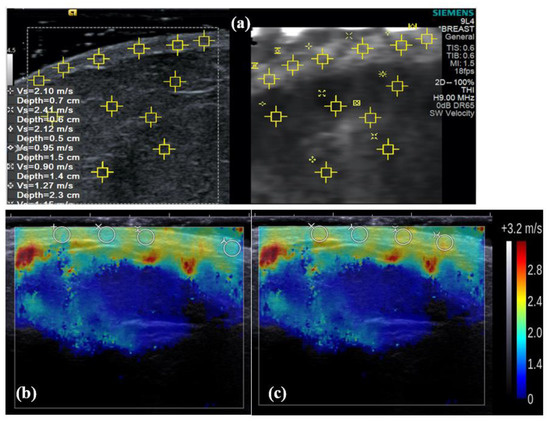

3.1. Difference in cs Estimates between Machines In Vitro

4.1. Difference in cs Estimates between Machines In Vitro

4.2. Rationale for the Exclusion of Artefacts from Aixplorer Elastogram Analysis